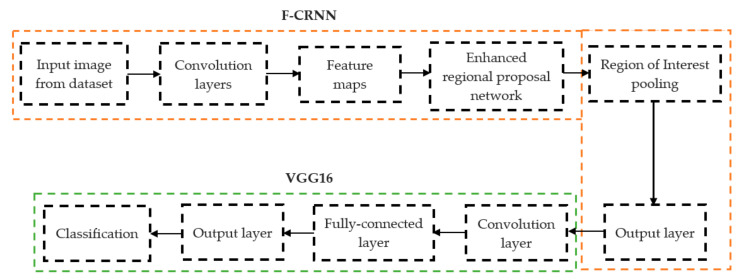

The initial step involved reducing an image to a size of 227 × 227 × 3. We used two convolutional neural networks for RA detection and classification in the second phase (Hybrid ResNet101 and VGG16). The image characteristics must be sufficient for accurate CBD grade determination and effective RA classification. We identified marginal joint space narrowing and categorized RA using these convolutional neural networks to extract instructive visual characteristics. To complete the RA classification process, two CNNs were used. First, we used ResNet101 with a domain adaptation strategy to identify marginal joint space contraction. Second, we used VGG16, which was trained using a domain adaptation technique, to classify RA. Finally, we evaluated the method’s effectiveness and contrasted our findings with those of other similar techniques already in use. Figure 1 shows a flowchart of the recommended process.

In deep learning, the F-CRNN is just one of the methods. The faster CRNN architecture is now the standard object identification method because of its ability to anticipate and score single or numerous items in an image. The enhanced-region proposal network and F-CRNN are two integral parts of the F-CRNN network. To ensure that the Quick R-CNN module receives only the best region suggestions, the ERPN generates them. To identify areas of interest in digital X-radiation pictures, we trained the ERPN. The end-to-end convolutional network (ERPN) can accurately anticipate the boundaries and scores of objects of interest at any coordinate. The ResNet101 network was used for F-CRNN feature extraction.

Each convolutional layer in ResNet101 was followed by a batch normalization and activation layer (ReLU). By avoiding parallel connections to the typical layers, this architecture facilitated more efficient training of deep neural networks. Features were extracted, and convolutional feature maps were generated using a combination of convolutional and max-pooling layers. Image characteristics were fed into ERPN, and region suggestions were generated as outputs. The ROI pooling layer took the feature vectors from the function maps. Each vector function was linked to the underlying layer. We individually trained the ROI detection model for the AP view’s medial and lateral compartments. When the algorithm produced several ROI detections, we chose the ROI with the highest prediction accuracy for each knee joint. To evaluate the proposed model, we counted the narrow regions of the marginal joint space that achieved IoU ≥ 0.70. As a result of the detection, we saved the predicted bounding boxes. We used weights that had already been trained on ResNet-101, and then used the domain adaptation method to fine-tune them. Figure 2 shows how modified ResNet-101 can find approaches with a narrow joint space in the knee. The most important part of the Faster R-CNN architecture is ERPN. ERPN predicts the scores of objects and their locations. The algorithm compares the narrow areas of the knee joint space in the medial and lateral compartments to find the narrow area in the middle. The best thing about this method is that it can find even the smallest changes in knee joint space.

2.2.2. RA Classification

For knee RA severity classification, we conducted this research using a modified version of the VGG16 architecture and a domain adaptation technique, as shown in Figure 3. The VGG16 model was made up of five convolutional layers, three max-pooling layers, and three fully connected layers—all the digital X-radiation images needed to be resized to (227 × 227 × 3). In our implementation, X-radiation image information for training purposes accounted for eighty percent of the total, while X-radiation image information for evaluating purposes accounted for twenty percent. Although there are sixteen layers in VGG16, only a subset of those layers is required for feature extraction. In order to shorten the amount of time needed for training and establish more control over the fitting process, we assigned a dropout ratio value of 0.5 to the completely connected layer (fcl6) and the fully connected layer (fcl7). The characteristics were taken from the fully connected layers designated fcl6 and fcl7, respectively. To categorize the retrieved features into 1000 categories, VGG16’s architecture used a fully connected layer (fcl8). Then, we conducted one last round of tuning on the pre-trained VGG16 model’s ability to classify RA by changing parameters in the model’s last three layers. The model’s last three layers were swapped out for a fully linked layer, a softmax layer, and a classification layer. In addition, a newly linked layer was assigned to five groups of RA grades for the dataset: Grade 0, Grade 1, Grade 2, Grade 3, and Grade 4. We trained the proposed network by using digital knee X-radiations, a small-batch test dataset, gradient descent, and maximal epochs. Our proposed network learning strategy used stochastic gradient descent, and we compared its performance to previous efforts. The proportion of knee X-radiation images from the test set for which the network correctly predicted the RA grade was used to calculate proposed work accuracy. The proposed approach achieved an overall accuracy of 99.10% in classifying knee RA cases. Table 5 illustrates the Visual Geometry Group (VGG16) CNN operation for RA grade classification. Figure 4, depicts the RA classification using VGG16 architecture.